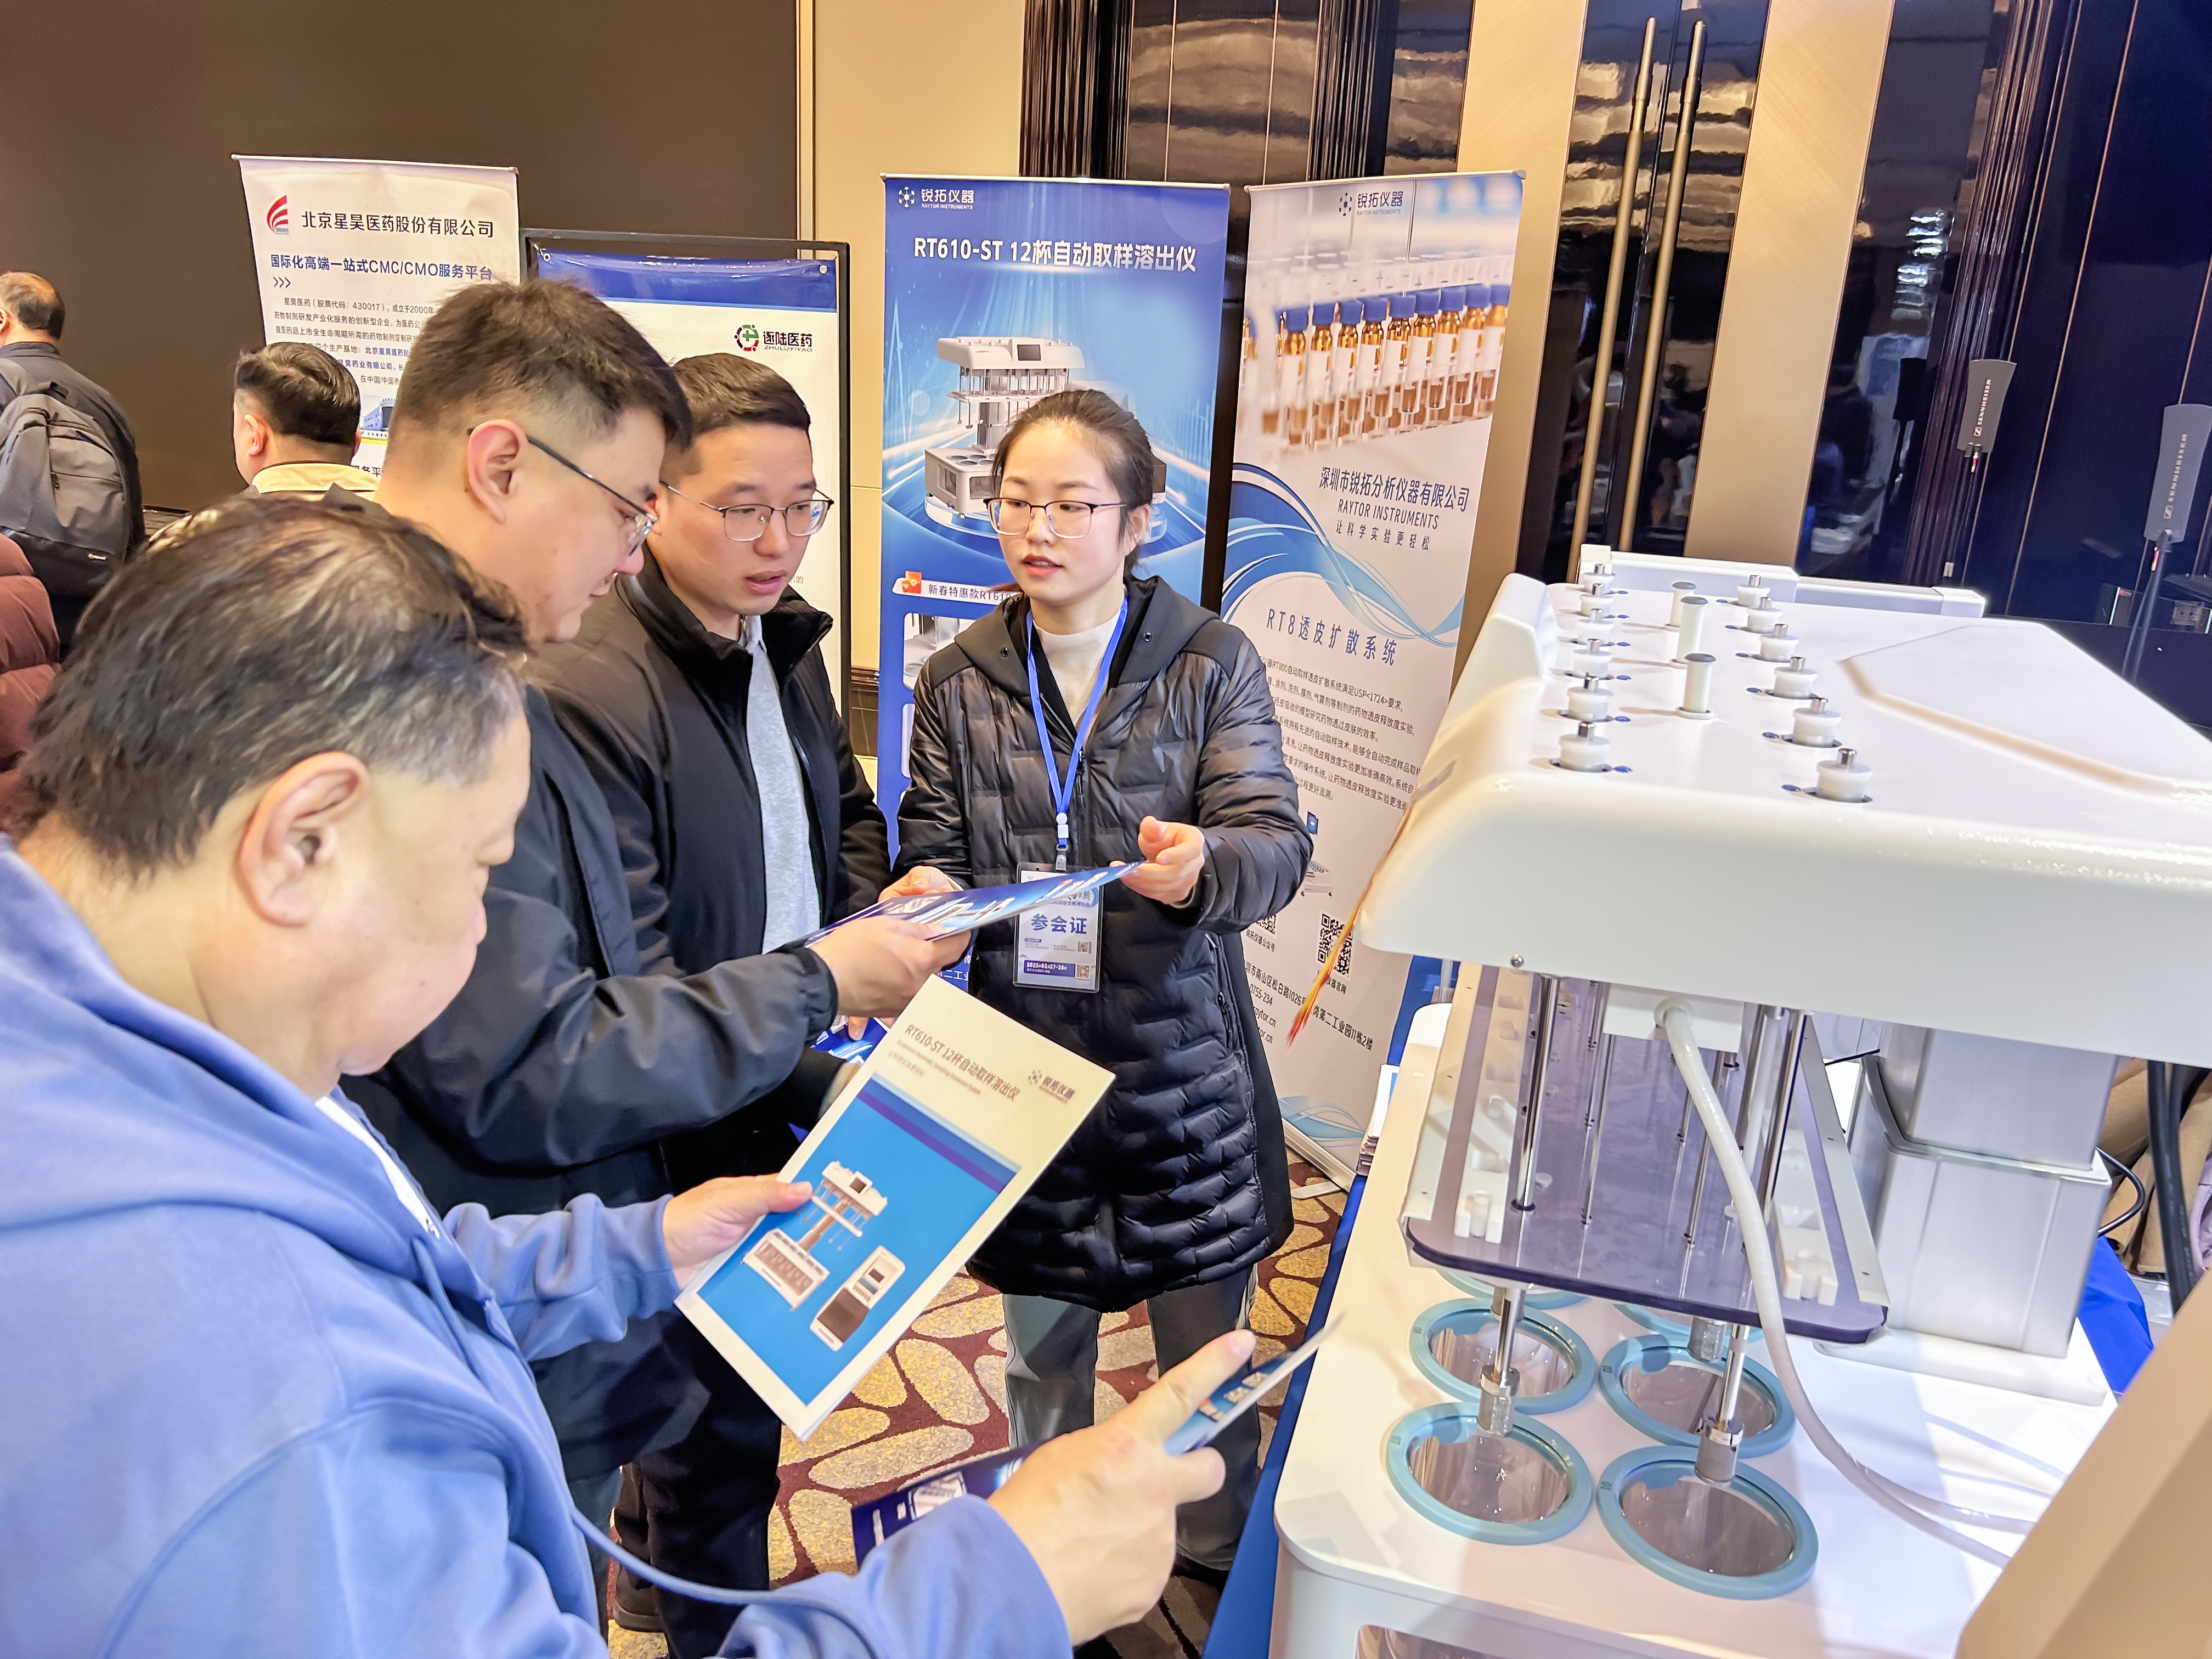

Raytor Instruments 12-cup autosampling विघटन उपकरण 2025 इंटरनेशनल फार्मास्युटिकल इनोवेशन एक्सपो में अपनी उत्कृष्ट ताकत से चमक रहा था।

27-28 फरवरी को, पहला 2025 इंटरनेशनल फार्मास्युटिकल इनोवेशन एंड प्रोजेक्ट ट्रांजेक्शन एक्सपो नानजिंग में सफलतापूर्वक संपन्न हुआ। स्टार उत्पादों के साथ रेटोर इंस्ट्रूमेंट्स RT610-ST 12-कप ऑटोसैंपलिंग विघटन उपकरण और RT800 ...